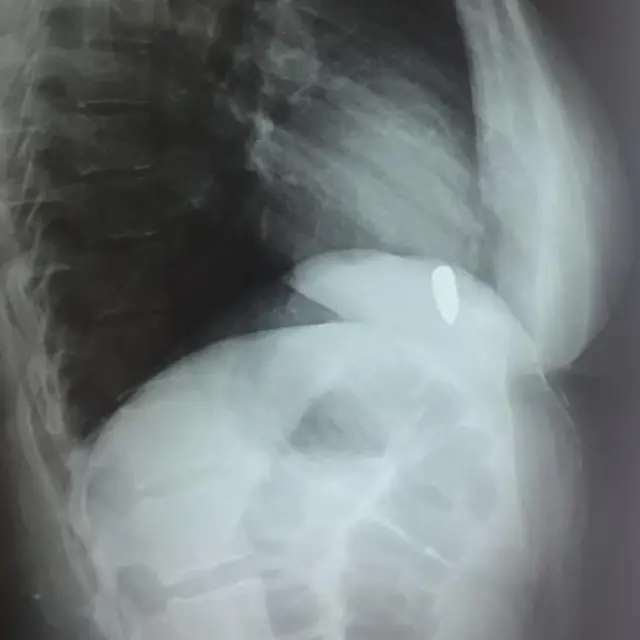

மருத்துவர் ஜாஹித் அலி ஷா, "அறுவை சிகிச்சை தொடங்கியபோது, இந்த அறுவை சிகிச்சை ஐந்து மணி நேரம் நீடிக்கும் என்று எதிர்பார்க்கப்படவில்லை. நாங்கள் அவருடைய மார்பைத் திறந்தபோது, தோட்டா சிக்கிக் கொண்டிருக்கும் என்று நாங்கள் எதிர்பார்த்த இடத்திலிருந்து அறுவை சிகிச்சையைத் தொடங்கினோம். அந்தப் பெண்ணின் இதயத்தைக் கையால் தொட்டபோது, அந்த தோட்டா இதயத்தில் நுழைந்தது என்பதை புரிந்துகொண்டேன்," என்கிறார்.

"எக்ஸ்-ரே எடுத்துப் பார்த்ததில், இதயத் துடிப்போடு தோட்டாவும் மேலேயும் கீழேயும் நகர்ந்தது தெரிந்தது. ஆறு மாதமாக இவர் இதை அனுபவித்து வந்ததால் எனக்கு அந்தப் பெண் குறித்து அதிக கவலை ஏற்பட்டது."

அவர் தோட்டா இருக்கும் இடத்தை அடைந்து அதை வெளியே எடுத்தபோது, நோயாளியின் இரத்த அழுத்தம் பதினைந்து வினாடிகளுக்குக் குறைந்து விட்டது என்று கூறினார். அப்போது, அவரது இதயப் பைகளில் ஒன்றில் அதிக ரத்த இழப்பு ஏற்பட்டதாகவும் அந்த பதினைந்து வினாடிகள் மிகவும் ஆபத்தானவை என்றும் அவர் கூறினார்.